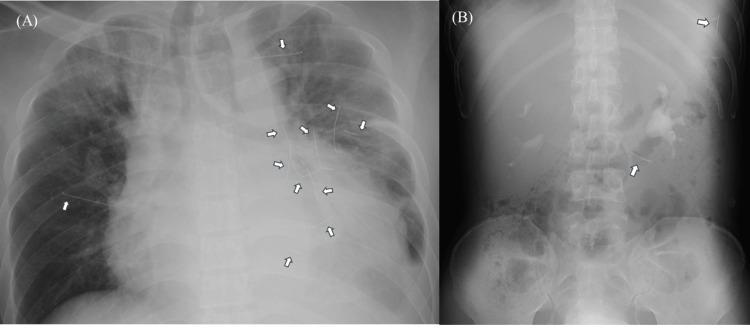

Retained needles are rarely observed in multiple locations. Furthermore, although case reports on retained needles have been published, there are no standardized guidelines for managing retained needles. A 42-year-old man with schizophrenia was referred to our hospital for intensive care because of a pericardial effusion and 12 needles from needle pricks being retained in both his chest and abdomen. First, he underwent emergency pericardial drainage. Thereafter, he underwent surgeries to remove a needle from the pericardium on day 7, abdominal needles on day 14, and intrapulmonary needles on day 30. He was transferred to a psychiatric ward on day 36 after it was confirmed that no needles remained in the body. We report a case of multiple needles being retained in multiple locations due to self-injury caused by schizophrenia. Future guidelines are needed to help clinicians manage patients with retained needles.

多部位滞留针极为罕见。此外,尽管已有关于滞留针的病例报告发表,但对于处理滞留针尚无标准化指南。一名42岁的精神分裂症男性因心包积液及胸部和腹部有12根针刺所致的滞留针而被转诊至我院进行重症监护。首先,他接受了紧急心包引流。此后,他在第7天接受了从心包取出一根针的手术,第14天取出腹部的针,第30天取出肺内的针。在确认体内无针残留后,他于第36天被转至精神科病房。我们报告一例因精神分裂症导致自我伤害而在多个部位滞留多根针的病例。未来需要制定指南以帮助临床医生处理滞留针患者。